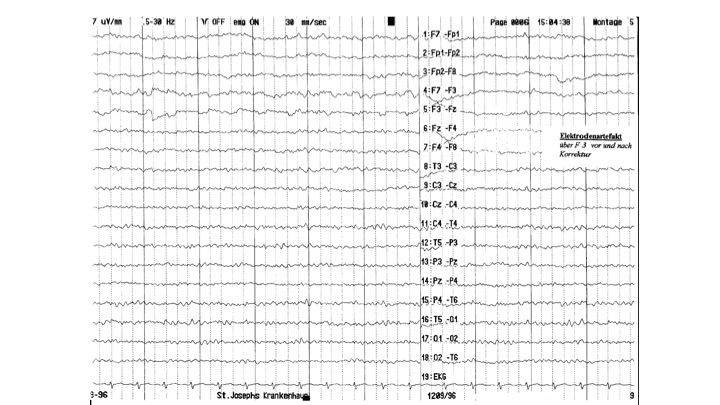

Artefakte im EEG | 57.65 zurück | weiter